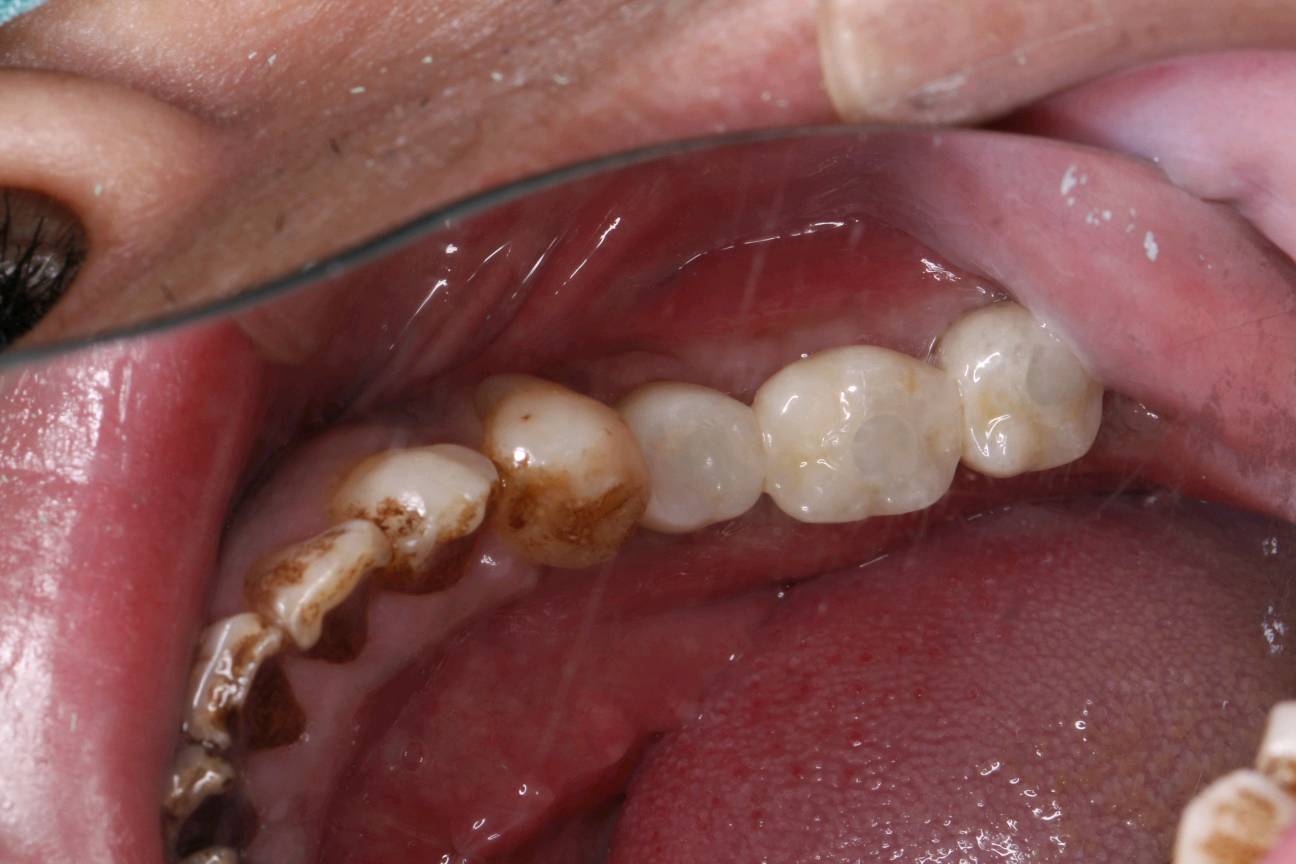

患者自愿选择安卓健种植体。牙槽嵴吸收较多,高度和宽度不足。拔出后植入骨粉骨膜。待骨条件良好后。35植入种植体4.0*10mm;36植入种植体4.6*10mm;37植入种植体4.6*8mm。待骨结合良好后。二期三期如期进行。余近日戴牙。

术后